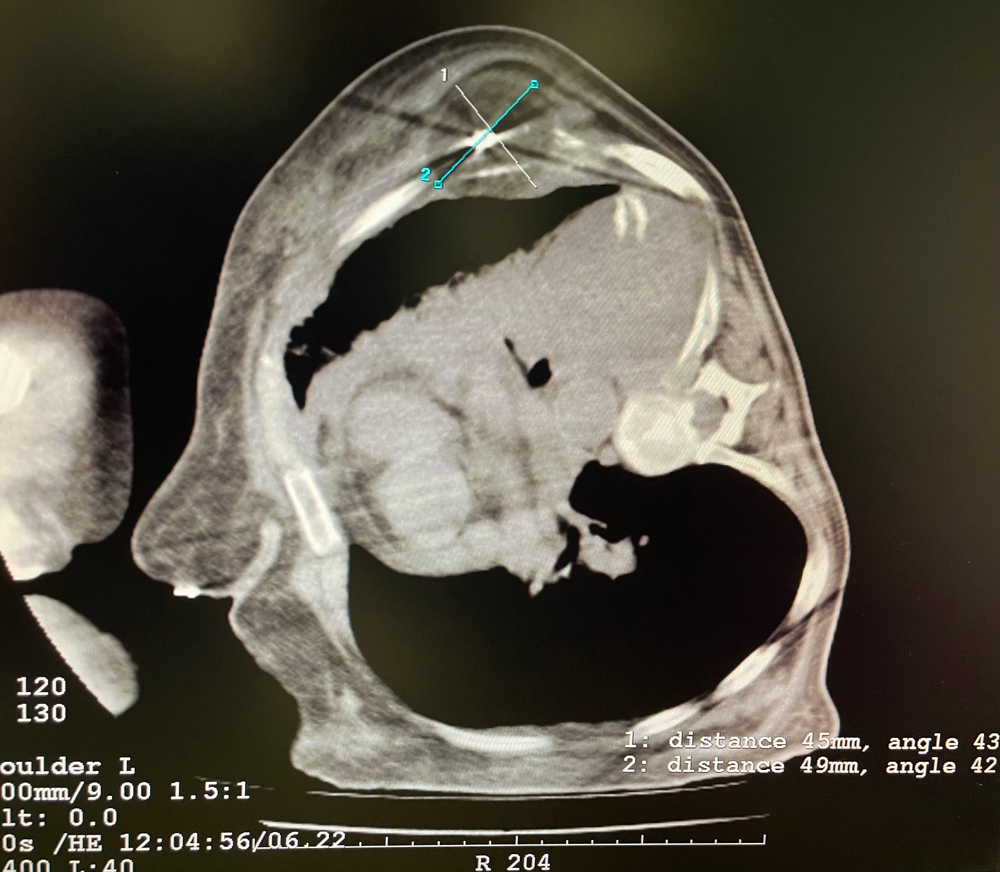

女,56歲,肺轉(zhuǎn)移瘤,骶骨、左側(cè)肋骨各一轉(zhuǎn)移灶,病灶大小均為5cm。骶骨轉(zhuǎn)移灶、肋骨轉(zhuǎn)移灶各進(jìn)行2個(gè)凍融循環(huán)。患者術(shù)后狀況良好。